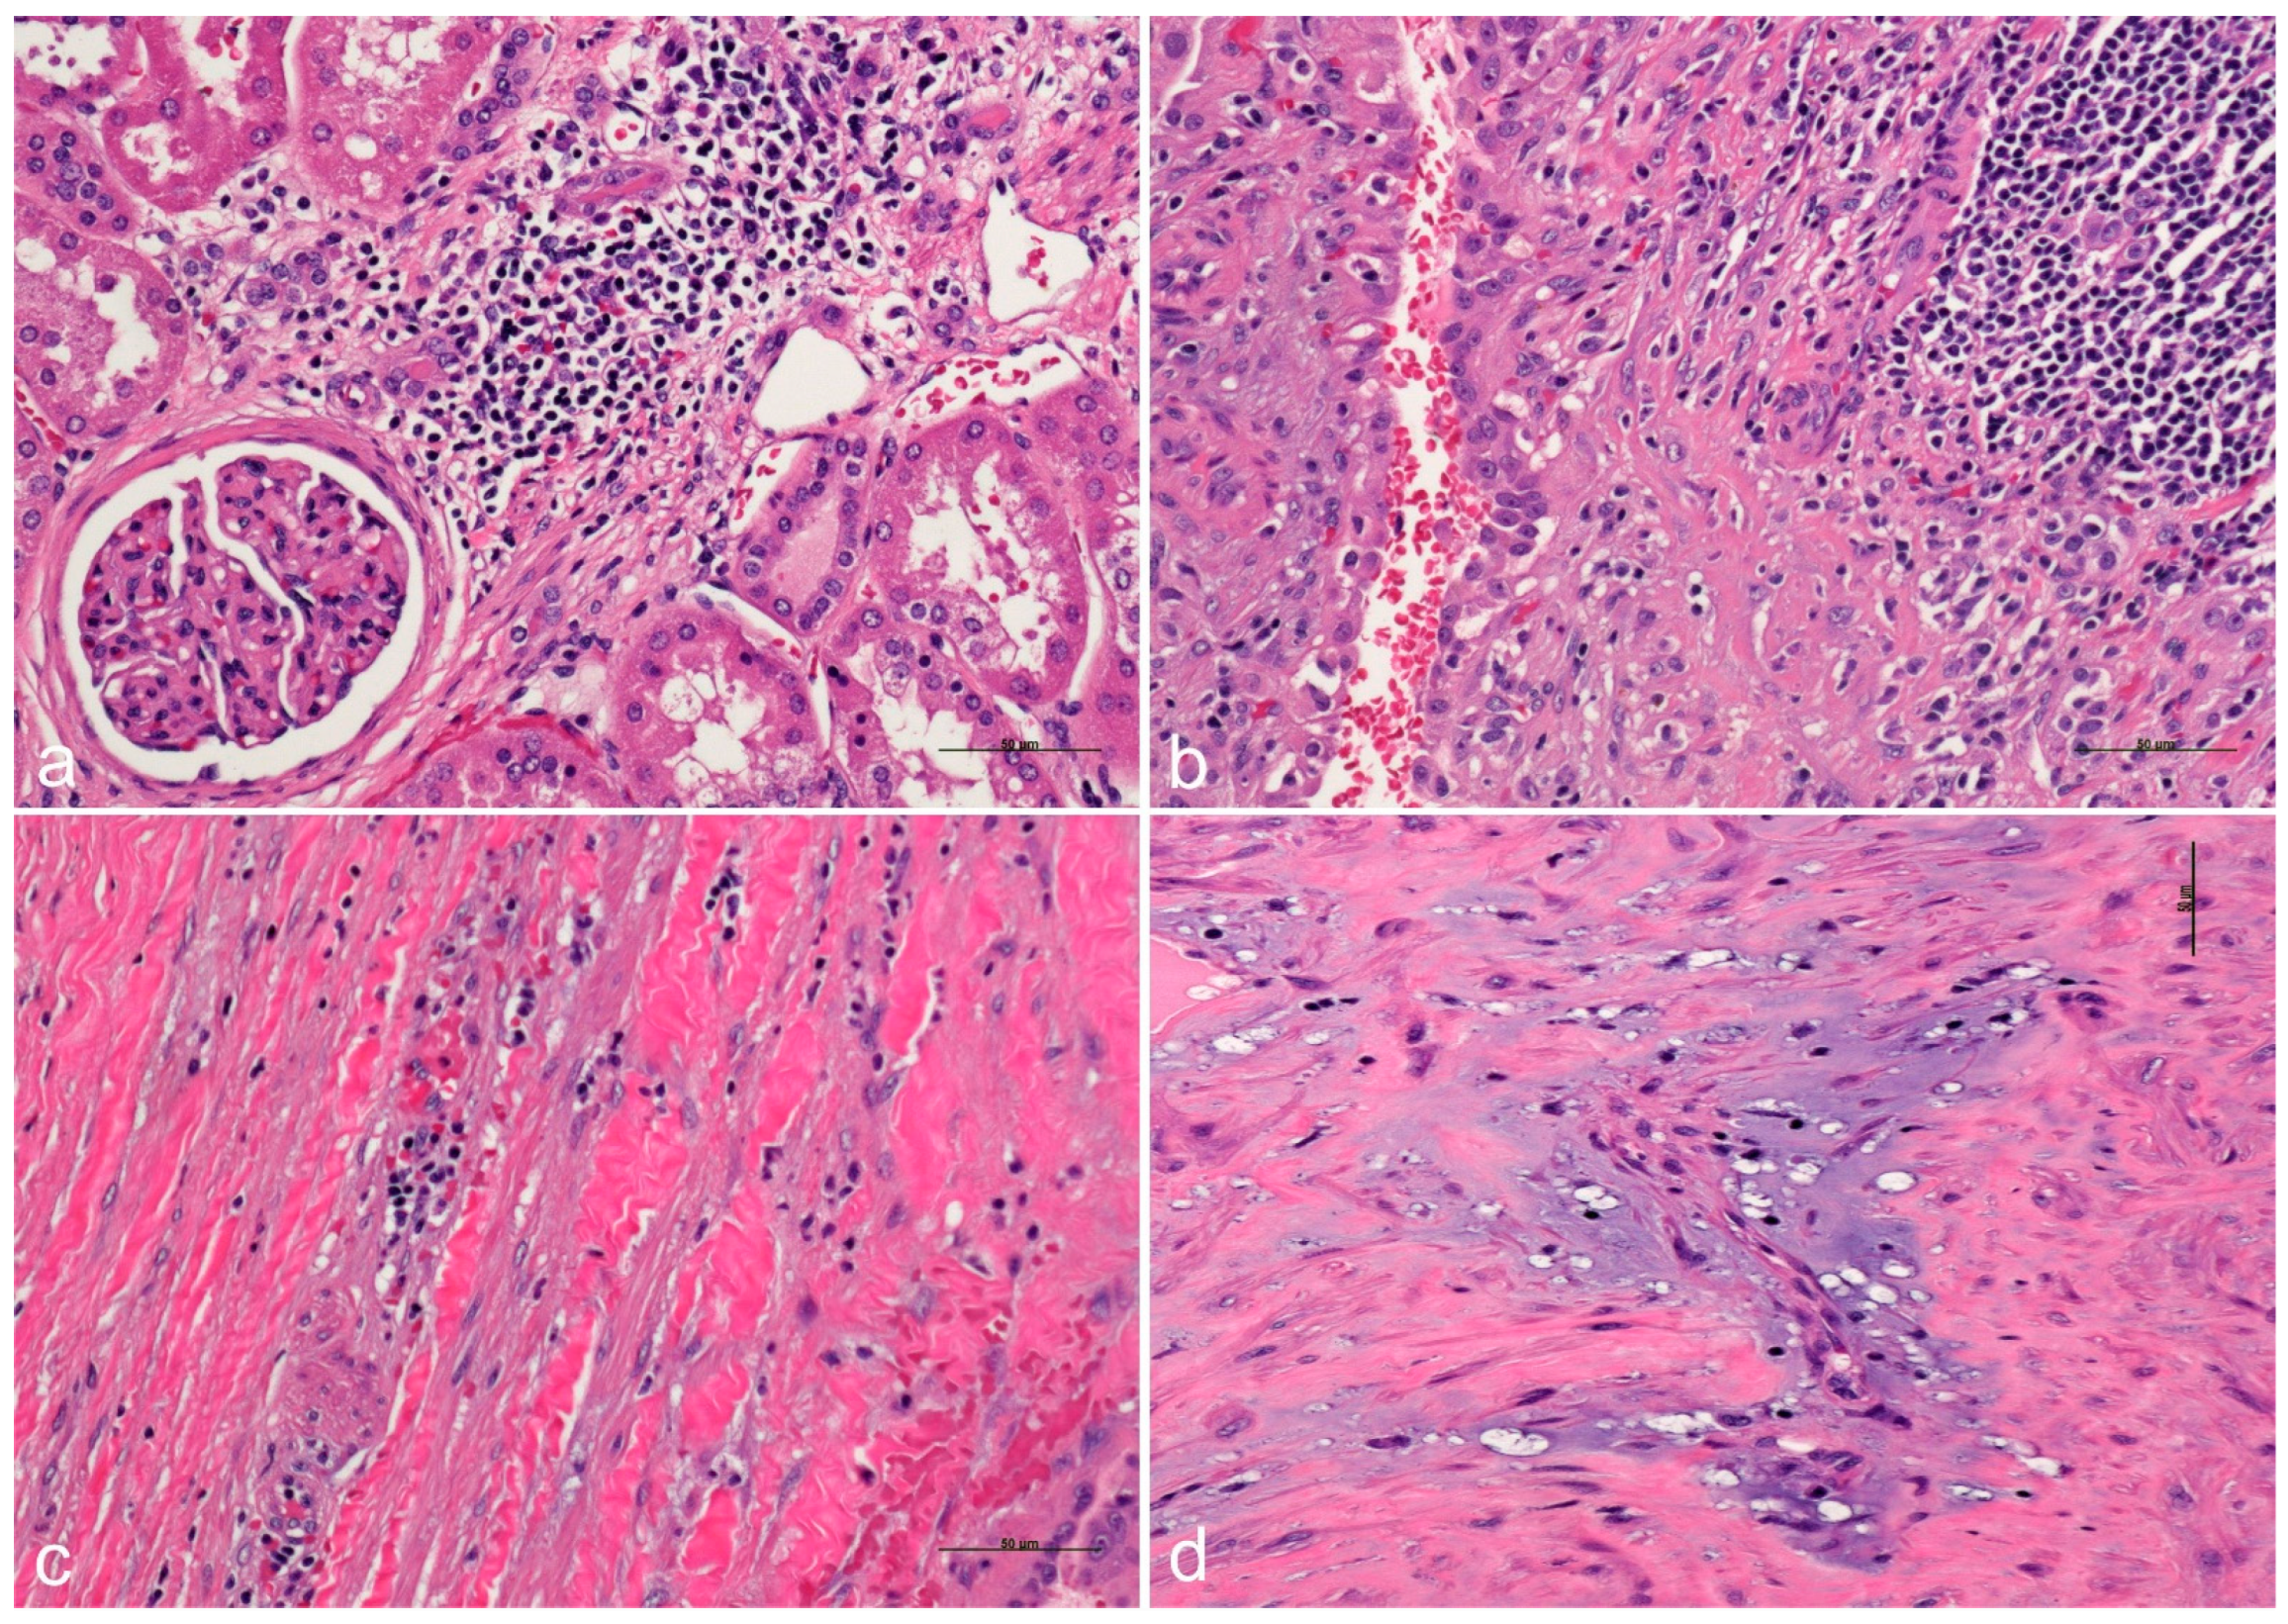

- Hakozaki, Y.; Uchiyama, K.; Yanai, A.; Yamada, D.; Kamijo, Y.; Ishibashi, Y. Sarcomatoid renal cell carcinoma with autosomal dominant polycystic kidney disease: A case report and literature review. CEN Case Rep. 2021, 10, 199–207. [Google Scholar] [CrossRef]

- Sahoo, N.; Patra, S.; Senapati, S.; Mishra, T.S. Multicentric papillary and chromophobe renal cell carcinomas in a patient with autosomal dominant polycystic kidney disease: Report of a rare case. Indian. J. Pathol. Microbiol. 2017, 60, 405–408. [Google Scholar] [CrossRef]

- Na, K.Y.; Kim, H.S.; Park, Y.K.; Chang, S.G.; Kim, Y.W. Multifocal renal cell carcinoma of different histological subtypes in autosomal dominant polycystic kidney disease. Korean J. Pathol. 2012, 46, 382–386. [Google Scholar] [CrossRef] [PubMed]